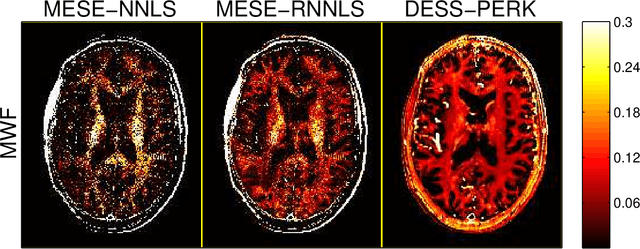

Abstract:Purpose: To investigate the feasibility of myelin water content quantification using fast dual-echo steady-state (DESS) scans and machine learning with kernels. Methods: We optimized combinations of steady-state (SS) scans for precisely estimating the fast-relaxing signal fraction ff of a two-compartment signal model, subject to a scan time constraint. We estimated ff from the optimized DESS acquisition using a recently developed method for rapid parameter estimation via regression with kernels (PERK). We compared DESS PERK ff estimates to conventional myelin water fraction (MWF) estimates from a longer multi-echo spin-echo (MESE) acquisition in simulation, in vivo, and ex vivo studies. Results: Simulations demonstrate that DESS PERK ff estimators and MESE MWF estimators achieve comparable error levels. In vivo and ex vivo experiments demonstrate that MESE MWF and DESS PERK ff estimates are quantitatively comparable measures of WM myelin water content. To our knowledge, these experiments are the first to demonstrate myelin water images from a SS acquisition that are quantitatively similar to conventional MESE MWF images. Conclusion: Combinations of fast DESS scans can be designed to enable precise ff estimation. PERK is well-suited for ff estimation. DESS PERK ff and MESE MWF estimates are quantitatively similar measures of WM myelin water content.